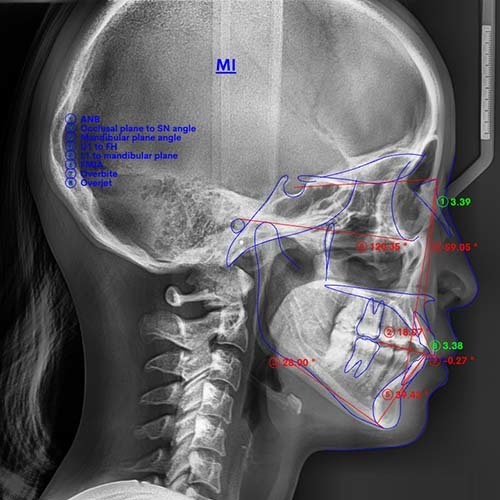

1,800症例(※)を手がける中で培った経験と、歯科用CTやセファロといった精密な検査機器を活用しながら、一人ひとりに合わせた矯正治療をご提供いたします。

治療を希望される場合は、精密検査を実施。レントゲンやCT撮影、お顔やお口の中の写真撮影などを行い、骨格や歯の状態を3次元的診断します。

これらの検査結果に基づき、矯正担当医が適切な治療計画を立案。シミュレーション動画をお見せしながら、歯の動き方や正確な費用・期間についてお伝えします。